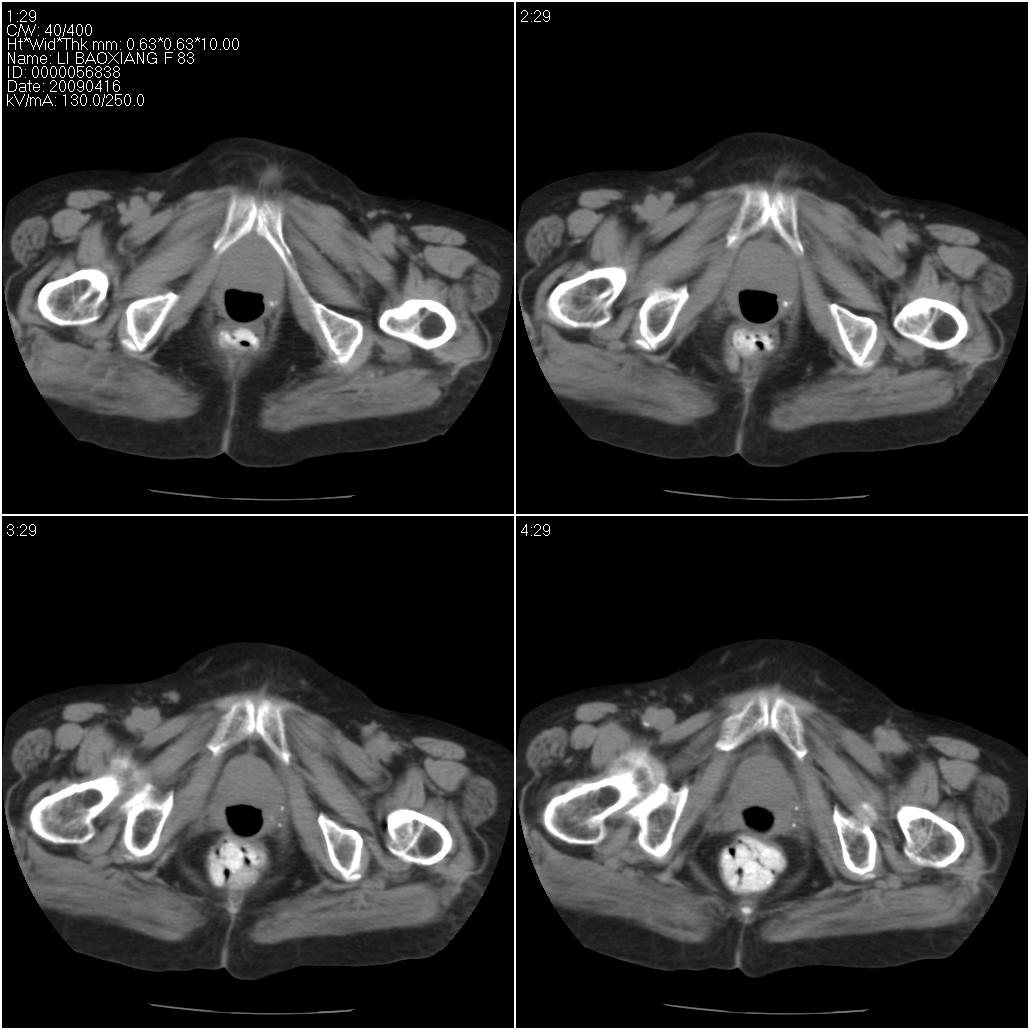

标题: CT19496:女性,83岁。阴道出血多年,患者一般情况良好。 [打印本页]

标题: CT19496:女性,83岁。阴道出血多年,患者一般情况良好。

考虑:乙状结肠癌累及子宫,建议钡剂灌肠。

乙状结肠癌累及子宫

乙状结肠癌侵犯子宫可能性大。